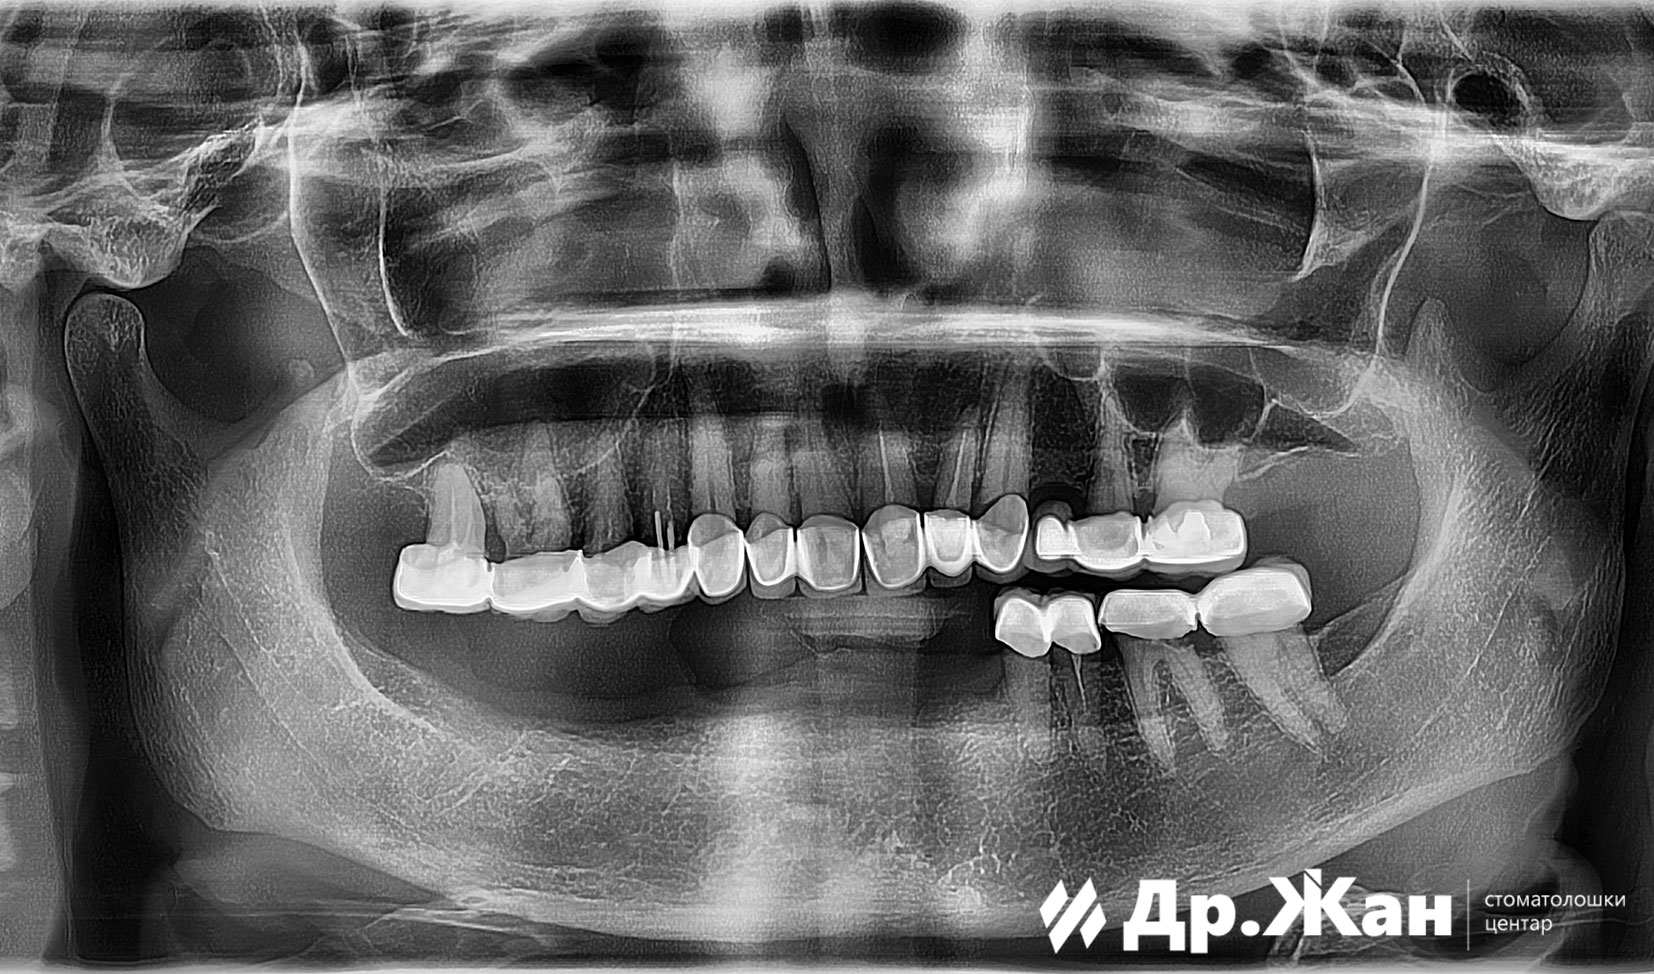

Оваа жена дојде во нашата клиника со нефункционална метал-керамичка конструкција во горната вилица и целосно нефункционална подвижна протеза во долната вилица.

По првичната анализа и рендгенските снимки, обезбедивме план за терапија кој вклучуваше поставување импланти и циркониумски коронки и мостови.

ПРЕД